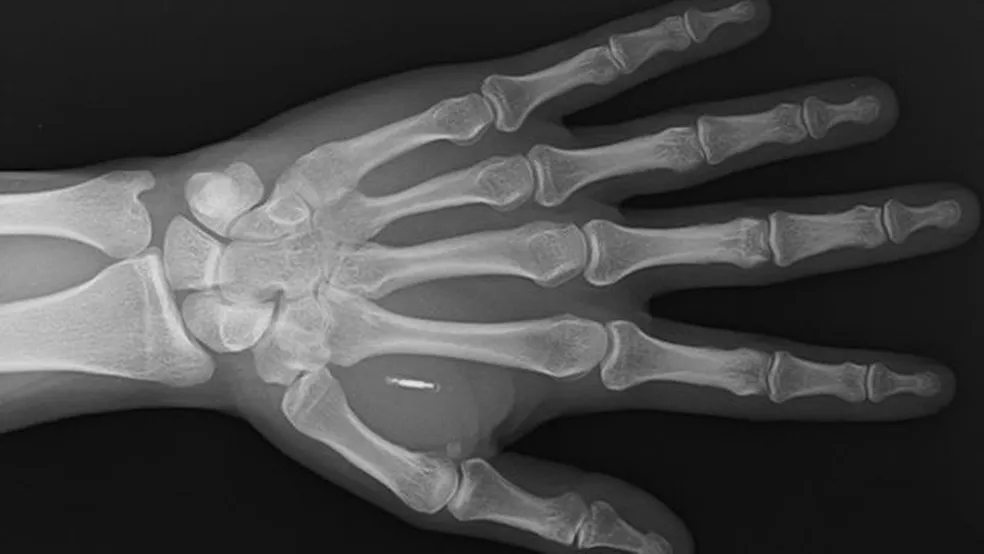

Mas, em muitos casos, o conceito envolve implantes de microchips no corpo. Esses dispositivos têm circuitos eletrônicos e uma peça para se comunicar com outros aparelhos por ondas de rádio.

O microchip é um conjunto de circuitos eletrônicos com módulos. Esses dispositivos costumam ser capazes de armazenar e transmitir informações.

Eles podem funcionar através de ondas de rádio, sensores integrados ou sinais elétricos. O chip pode ser implantado no corpo em poucos minutos e o processo geralmente acontece em estúdios de aplicação de piercing.

O microchip possui uma espécie de vidro que é biocompatível, ou seja, não cria reação alérgica ou outra reação imunológica, disse ao g1 Fernanda Matias, professora de biotecnologia na Universidade de São Paulo (USP). No Brasil, não há leis que regulamentam os implantes.

Como funciona o chip implantado na mão — Foto: Arte/g1